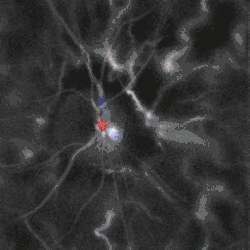

Blood flow in the retina and choroid in the optic disc region can be revealed non invasively by near-infrared laser Doppler imaging.[4] Laser Doppler imaging can enable mapping of the local arterial resistivity index, and the possibility to perform unambiguous identification of retinal arteries and veins on the basis of their systole-diastole variations, and reveal ocular hemodynamics in human eyes.[5] Furthermore, the Doppler spectrum asymmetry reveals the local direction of blood flow with respect to the optical axis. This directional information is overlaid on standard grayscale blood flow images to depict flow in the central artery and vein.[6]

Local direction of blood flow with respect to the optical axis revealed by the Doppler spectrum asymmetry in out-of-plane retinal vessels by holographic laser Doppler imaging.[6] -